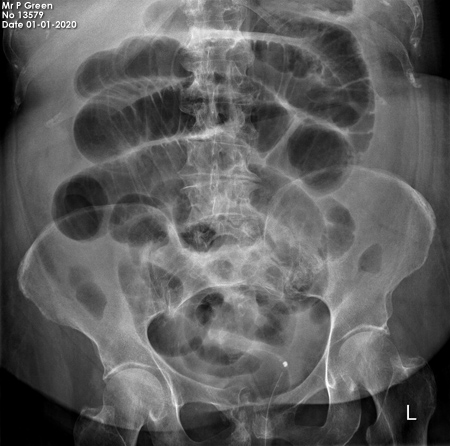

Abdominal X-ray - Scenario 2

- Take a moment to view the image

- When you are ready - present your findings

- State your summary clearly before clicking the 'Next' button